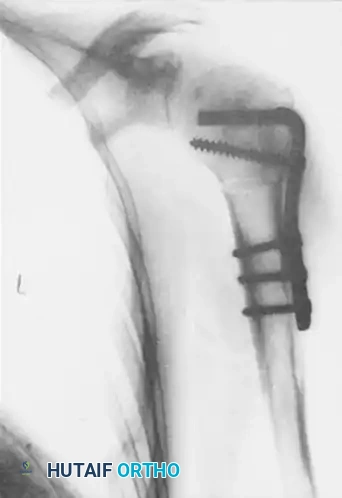

The osteotomy is rigidly fixed using an angled blade plate or a modern locking plate system.

Figures above illustrate the internally fixed humerus after transverse osteotomy and internal rotation of the humeral shaft using an angled plate construct. This effectively alters the articular arc, preventing the reverse Hill-Sachs lesion from engaging the posterior glenoid rim.